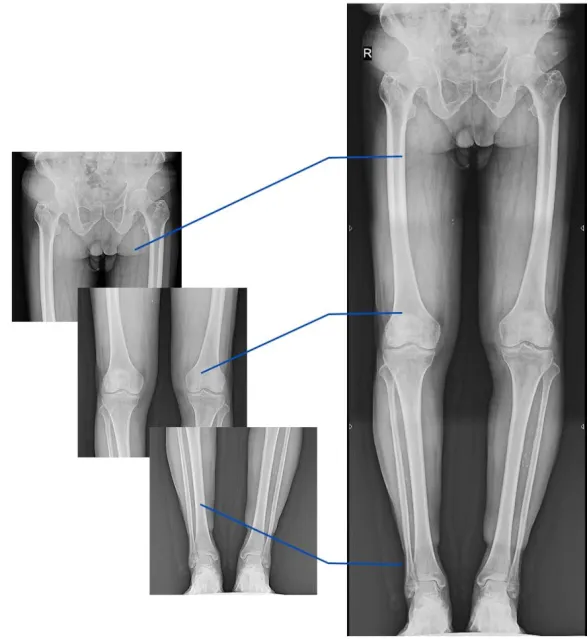

临床发现,脊柱侧弯畸形多发生于青少年,若得不到及时治疗将会影响生长发育,严重者还有可能导致心肺功能受损;而骨性关节炎、风湿性关节炎以及双下肢畸形(膝关节内外翻、X型腿、O型腿等)为骨科常见病,且发病率呈现逐年升高的趋势,常常累及下肢髋、膝、踝等负重关节,影响患者生活,甚至丧失工作能力。在脊柱及下肢畸形诊断、治疗中,均需要拍摄X线平片以便分析病情、明确诊断和观察治疗效果。

我院放射科顺应新趋势,购置高性能多功能动态平板DR。动态DR具有全身拼接功能,尤其适用于全脊柱和全下肢摄影,辅助脊柱畸形矫形治疗、关节置换手术、康复检查,为临床提供高精度图像。